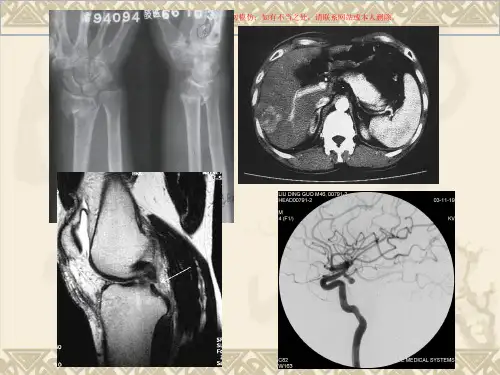

❖ 医学影像学: ❖ 影像诊断学 ❖ 介入放射学

影像诊断学

❖ 运用各种成像技术,使人体内部结构和器 官成像,借以了解人体解剖与生理功能状况 及病理变化,以达到诊断的目的,是特殊的 诊断方法。